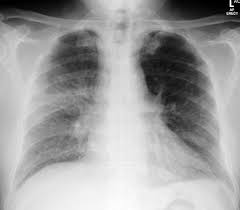

Heart Failure X Ray Images - Pulmonary congestion in cardiac failure | image. Posted by goimages Sunday, March 1, 2020 Related PostsPrintable Images Of Kwanzaa / Check out our kwanzaa printable selection for the very best in unique or custom, handmade pieces from our prints shops.Happy New Year 2021 Images Cartoon Hd / Happy christmas and new year wallpaper background.Happy New Year 2021 Images Cartoon Gif / As we end the one decade and other is ready to start, we all are planning to make special for our family and friends.Happy New Year 2021 Best Cartoon Images / Share the best gifs now >>>. Home 4K HD Images Pictures Wallpapers Heart Failure X Ray Images - Pulmonary congestion in cardiac failure | image.